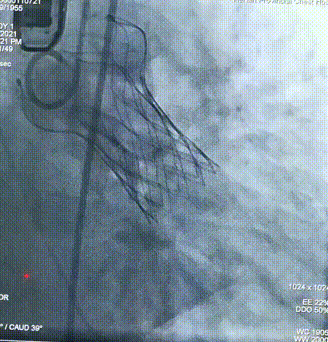

球囊预扩

瓣膜定位

经评估后植入左主干烟囱支架